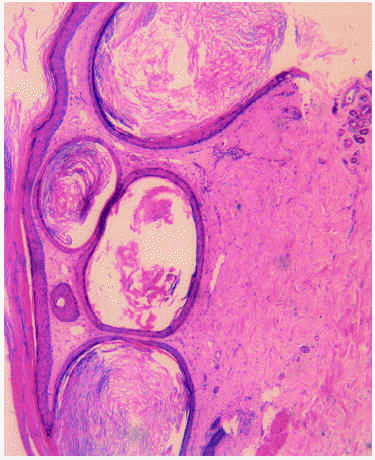

Una mujer de 58 años acudió a nuestra consulta por presentar, desde hacía 3 meses, varias placas eritematosas con quistes miliares agrupados en su superficie, localizadas a lo largo de las cuatro extremidades. Negaba el uso de ningún cosmético y no recordaba ningún traumatismo previo o quemadura. Como antecedentes personales, no refería alergias medicamentosas conocidas ni hábitos tóxicos. Padecía leucemia mieloide crónica de 6 años de evolución, y había iniciado tratamiento paliativo con 6-mercaptopurina un mes antes de que aparecieran las lesiones cutáneas por progresión de su enfermedad hematológica. Asimismo, debido a un síndrome ansioso-depresivo recibía citalopram desde hacía varios años. En la exploración física se apreciaban varias placas eritematosas, ovaladas, bien definidas, de 3 cm de diámetro máximo, en cuyo interior había quistes miliares confluentes (fig. 1). Presentaba asimismo algunos quistes miliares aislados en la región facial. El resto de la exploración fue normal. Se efectuó biopsia cutánea que, teñida con hematoxilina-eosina (fig. 2), mostró varios quistes alineados por epitelio estratificado, llenos de queratina, que formaban capas concéntricas laminadas. No se encontraron más alteraciones.

Fig. 1.--Varios quistes miliares agrupados sobre una placa eritematosa en la cara anterior de muslos.